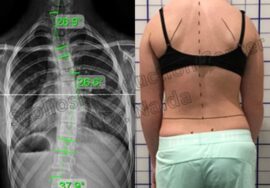

يُعد اعوجاج العمود الفقري عند المراهقين (الجنف) من أكثر مشكلات الظهر شيوعًا في فترة النمو. يظهر عادة في سن المراهقة دون سبب واضح. ومع ذلك، تشير الأبحاث الحديثة إلى أن المشكلة لا تتعلق فقط بشكل العمود الفقري، بل تمتد لتؤثر على توازن الجسم وطريقة تحكم المراهق في حركة رأسه ورقبته.

أراد الباحثون معرفة ما إذا كان المراهقون المصابون بالجنف يعانون من ضعف في الإحساس بحركة الرقبة مقارنةً بالمراهقين الأصحاء.

أظهرت النتائج أن المراهقين المصابين بالجنف يعانون من ضعف في الإحساس بحركة الرقبة مقارنة بالأصحاء.

لاحظ الباحثون أن بعض المشاركين لم يتمكنوا من إعادة الرأس بدقة بعد تحريكه، وكانت الانحرافات في الوضعية أكبر من المعتاد.

كما وجدوا أن ضعف الإحساس يزداد مع ارتفاع درجة الانحناء في العمود الفقري، مما يشير إلى أن الاعوجاج قد يؤثر تدريجيًا على توازن الرأس والجسم معًا.

عندما لا يتمكن الجسم من ضبط وضع الرأس بدقة، يتوزع الضغط بشكل غير متوازن على العمود الفقري، مما قد يؤدي إلى تفاقم الانحناء.أهمية فحص الرقبة أثناء التشخيص:

يجب أن يشمل تقييم المريض اختبار إحساس الرقبة، بجانب الأشعة وفحص زاوية الانحناء، للحصول على خطة علاج أدق.بعد الجراحة: